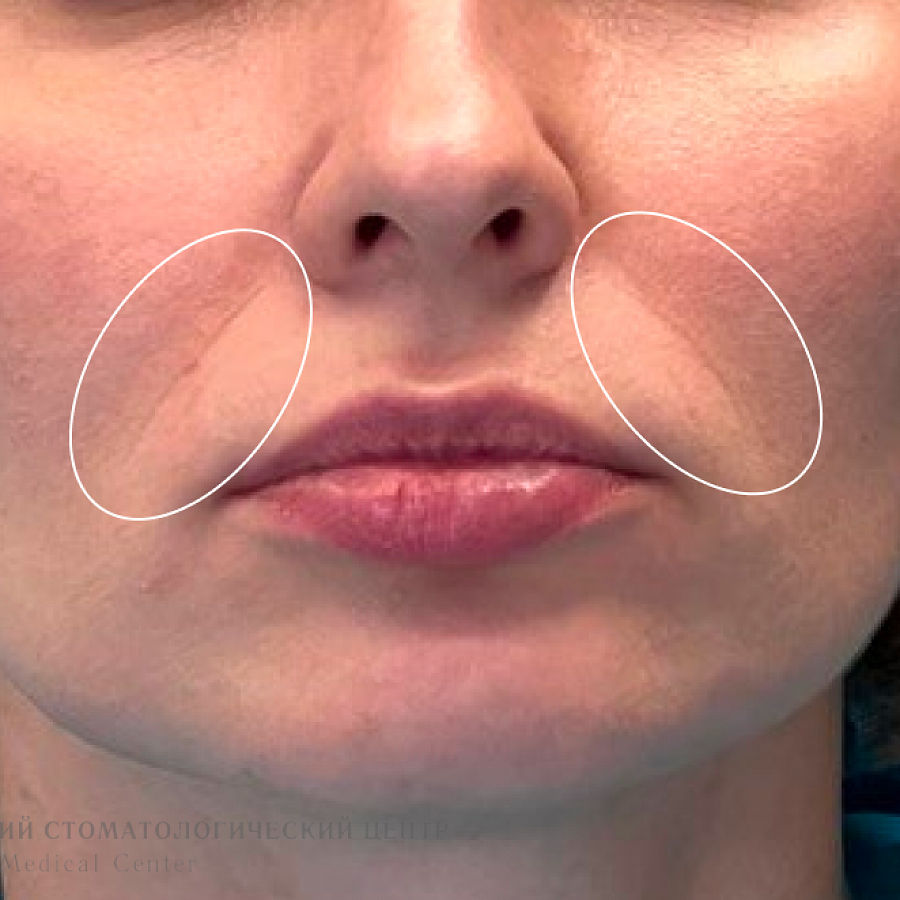

- Восстановлена высота нижней трети лица

- Разгладились носогубные складки, лицо приобрело более молодое и симметричное выражение

Результат лечения